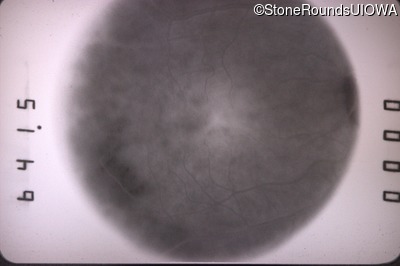

Fundus Photography - Right - 20/40 -2

Exemplar